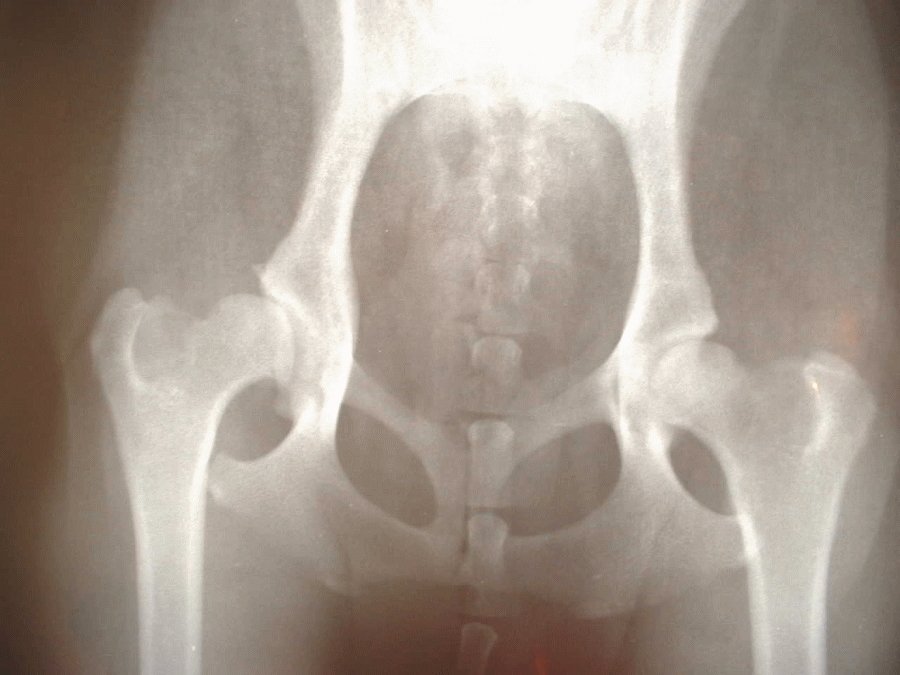

くる病とは

ビタミンDやリン・カルシウムの不足が原因で骨がうまく形成できず、骨が柔らかくなってしまう病気のことです。骨が成長する子犬期で発症しやすいです。

このビーグルの病理解剖の結果、背骨・肋骨などが大きく曲がり、足の関節がひどく腫れていたそうです。